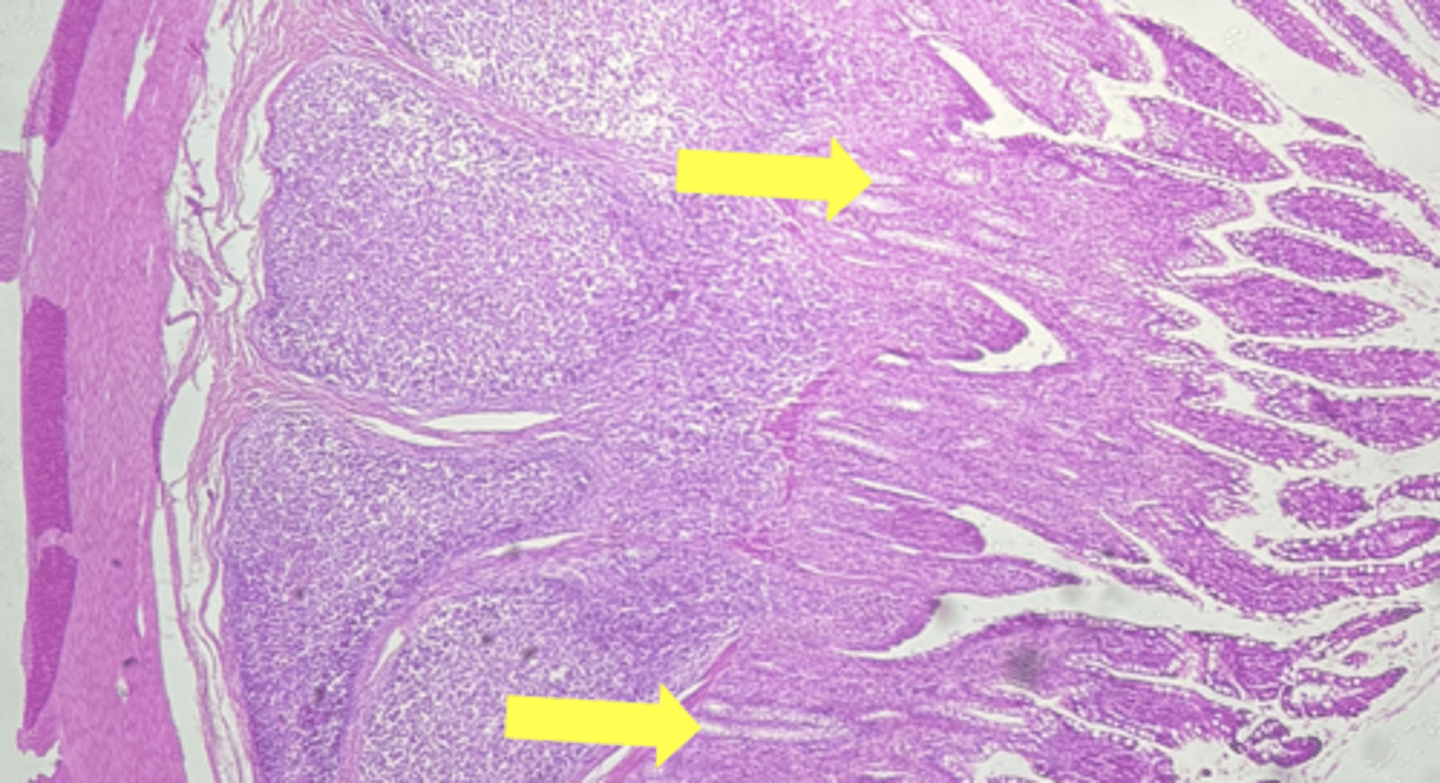

ileum-small intestine

type of tissue

payers patch (KEY CHARACTERISTIC)

(ilium)

circular layer

(ileum)

longitudinal layer

villi